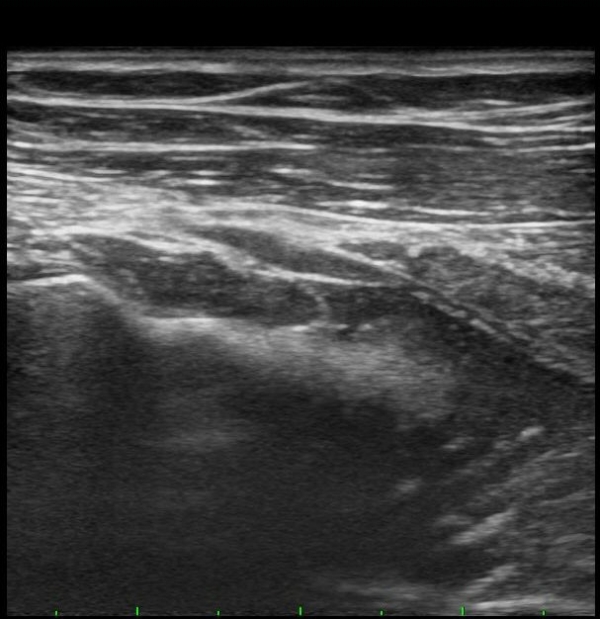

ŽÃËÀÚ¸¦ Á» ´õ ¸»´ÜÀ¸·Î À̵¿ÇÏ´Ï Èİñ°£½Å°æÀÌ È¸¿Ü±Ù ¸»´Ü¿¡¼­ Ç¥ÃþÀ¸·Î ³ª¿À´Â °ÍÀÌ °üÂûµÊ(±×¸² 3).